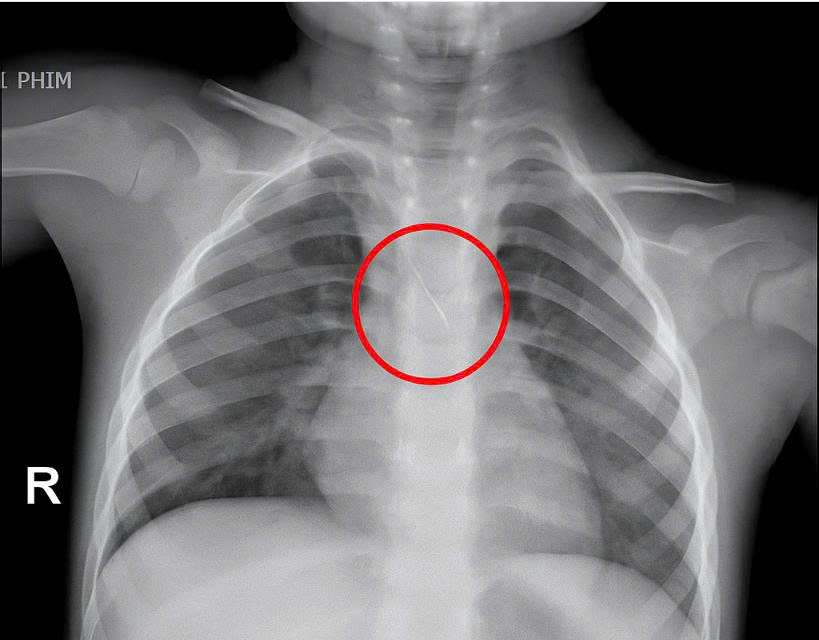

Dị vật trong đường thở cháu bé.

Trước đó bệnh viện tiếp nhận bé N.Q.T.Đ. (3 tuổi), trú tại xã Cửa Việt, Quảng Trị, trong tình trạng ho nhiều, ho sặc. Kết quả chụp phim cho thấy một dị vật kim loại dài khoảng 22mm nằm ở góc carina (vị trí chia đôi khí quản) đe dọa gây tắc nghẽn đường thở của trẻ.

Ngay lập tức, các bác sĩ hội chẩn liên khoa và quyết định nội soi phế quản cấp cứu. Dị vật được phát hiện có một đầu nhọn cắm vào 1/3 dưới khí quản, đầu còn lại nằm trong phế quản gốc trái, được xác định rất nguy hiểm.